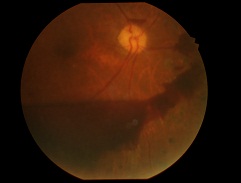

先日ハードレンズを処方した方の写真です。